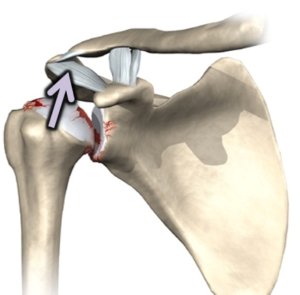

In de meerderheid van de gevallen (95%) ontwricht de kop naar voor (anterieure luxatie), in een beperkt aantal gevallen (5%) ontwricht de kop naar achter (posterieure luxatie). Als de schouder uit de kom gaat kan het labrum met het kapsel erop afscheuren van de kom (bankart letsel). Soms kan er zelfs een stukje bot van de kom mee afbreken (bony bankart letsel).

Bijkomend ontstaat er een indeuking in de bol (humeruskop) van de schouder omdat deze tijdens de ontwrichting tegen de rand van de kom (glenoid) wordt geduwd (hill sachs letsel). Bij oudere mensen kan een ontwrichting ook gepaard gaan met een scheur in de rotator cuff.